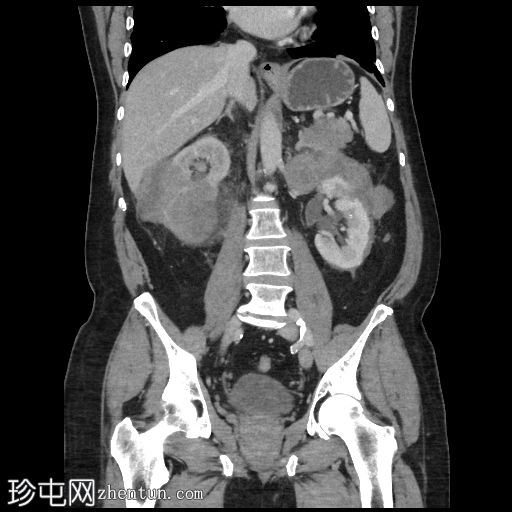

轴位增强扫描(门静脉期)

右肾可见不规则分叶状低密度浸润性病变,超出肾包膜,并与右肝下叶相邻。

左肾可见弥漫性浸润性病变,以上极为中心。左肾浸润性病变与胰尾相邻,胰尾可能受累,表现为胰腺后缘不规则、脂肪间隙消失。此外,浸润性病变与左侧肾上腺外侧肢相邻。

左肾偶然发现一小结石和肾囊肿。

脾脏下极可见一密度不明、呈分叶状/浸润性改变的肿块。

本例为肾淋巴瘤,具体为弥漫性大B细胞淋巴瘤(DLBCL)。

鉴于其浸润性病变,高度怀疑为淋巴瘤。原发性肾脏恶性肿瘤(例如肾细胞癌、肾嗜酸细胞瘤)的可能性较小。肾脏肿块活检证实为肾脏DLBCL。